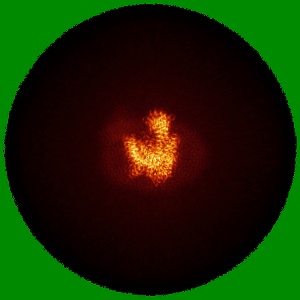

Cryo-EM structure of the mammalian peptide transporter PepT2 bound to cefadroxil

Sample: Complex of the mammalian peptide transporter PepT2 with nanobody and bound cefadroxil

Structural basis for antibiotic transport and inhibition in PepT2.

Parker JL , Deme JC , Lichtinger SM , Kuteyi G, Biggin PC , Lea SM , Newstead S

(2024) Nat Commun , 15 , 8755 - 8755